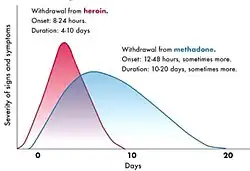

The withdrawal syndrome from heroin may begin within as little as two hours of discontinuation of the drug; however, this time frame can fluctuate with the degree of tolerance as well as the amount of the last consumed dose, and more typically begins within 6–24 hours after cessation. Symptoms may include sweating, malaise, anxiety, depression, akathisia, priapism, extra sensitivity of the genitals in females, general feeling of heaviness, excessive yawning or sneezing, rhinorrhea, insomnia, cold sweats, chills, severe muscle and bone aches, nausea, vomiting, diarrhea, cramps, watery eyes,[70] fever, cramp-like pains, and involuntary spasms in the limbs (thought to be an origin of the term "kicking the habit"[71]).[72][73]

Both morphine and 6-MAM are μ-opioid agonists that bind to receptors present throughout the brain, spinal cord, and gut of all mammals. The μ-opioid receptor also binds endogenous opioid peptides such as β-endorphin, leu-enkephalin, and met-enkephalin. Repeated use of heroin results in a number of physiological changes, including an increase in the production of μ-opioid receptors (upregulation).[86] These physiological alterations lead to tolerance and dependence, so that stopping heroin use results in uncomfortable symptoms including pain, anxiety, muscle spasms, and insomnia called the opioid withdrawal syndrome. Depending on usage it has an onset 4–24 hours after the last dose of heroin. Morphine also binds to δ- and κ-opioid receptors.